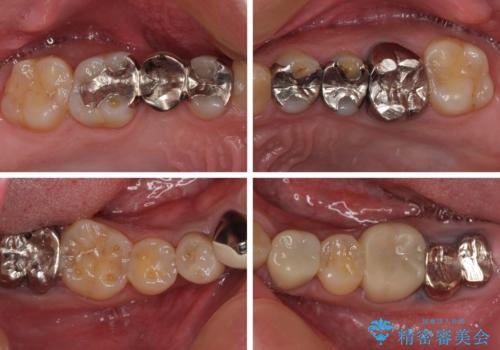

- 近医にて下顎奥歯の抜歯が必要と言われたとのことで来院された患者様です。

診察の結果、奥歯は左右ともに抜歯が必要な状態でした。

他の銀歯も気になっており、セラミックにしたいとの要望があり、詳しくお話をすると、デコボコの歯ならびも整えたいとのことでした。

抜歯が必要な歯は事前に抜歯をし、その後ワイヤー装置にて歯列矯正を行い、途中でインプラントを埋入し、オールセラミッククラウンにて補綴治療を行うこととしました。